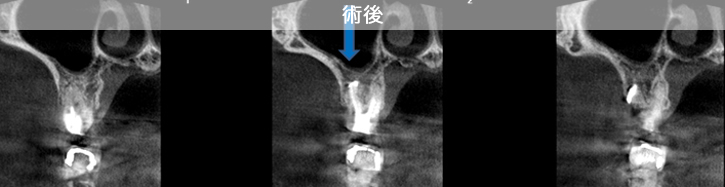

原因は赤の矢印が指す、根の周りの病巣でした。

治療後は青い矢印が指す場所には、黒い病巣が消失しています。

| 治療説明 | 自覚症状で歯が浮いた感じがしていました。上顎大臼歯・頬側根の根尖部にX線透過像の病巣があります。根充剤を除去・拡大清掃・根管充填を行いました。根尖から根充剤がはみ出ていますが、根尖部のX線透過像は見られなくなりました。そこ後、自覚症状もなくなりました。 |

|---|---|

| 治療期間 | 6〜24ヶ月 |

| 治療費用 | 150,000〜300,000円 |

| 治療に伴うリスク | 根管内からの治療で根尖病巣が治らない場合は、外科的に根尖病巣を除去する必要があります。 再根管治療を繰り返す場合、歯根の厚みが薄くなり、歯根破折のリスクが高まります。 |